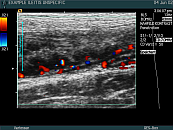

• renal transplant parenchyma

renal transplant parenchyma

• renal transplant

renal transplant